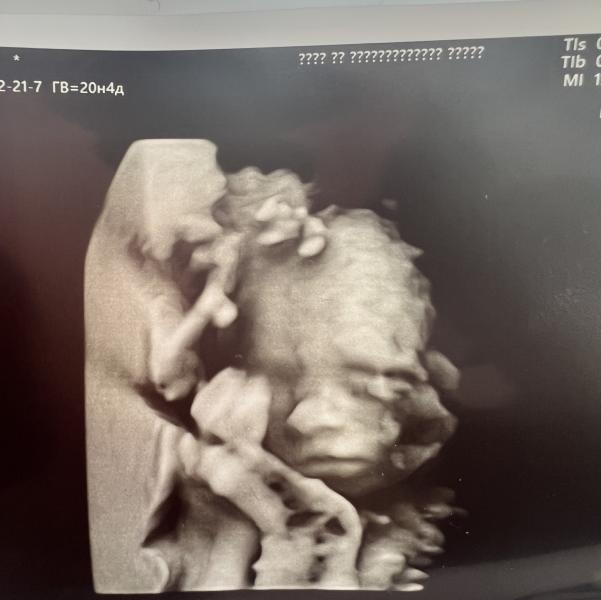

Второй скрининг: 341 гр мальчик, шейка 38 мм, поднялась плацента!

Второй скрининг ✅

Весит 341 гр наш крошка

Подтвердили, что это мальчик и сегодня я заказала уже первые бодики🥰

Шейка стала 38, а на 1 была 31.

Так же поднялась плацента 🤞🏻